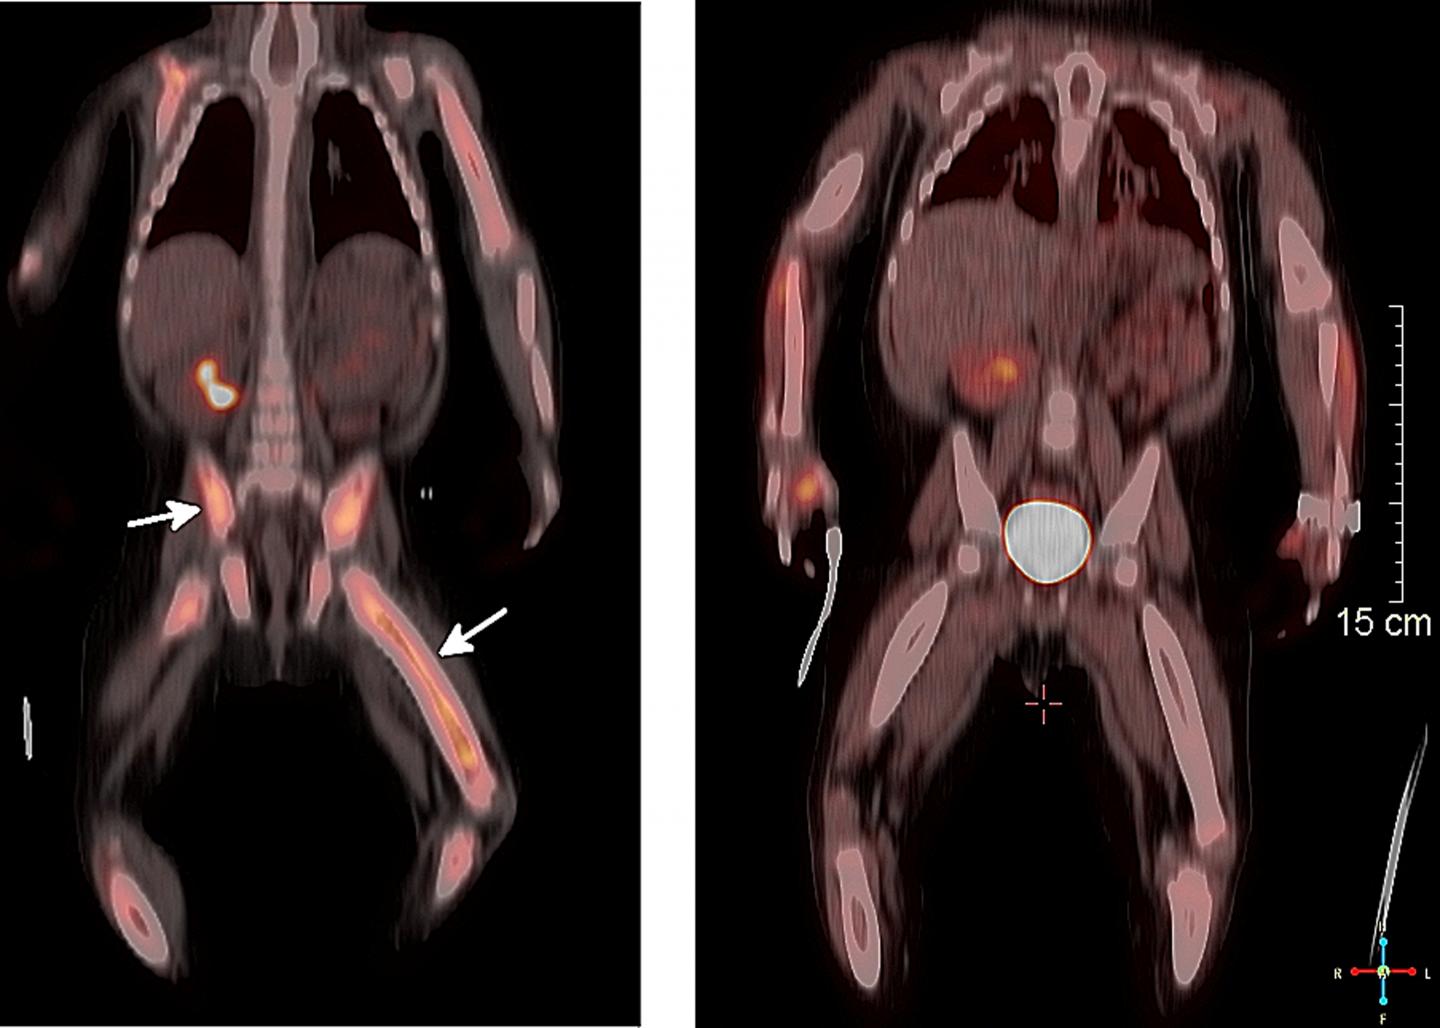

Study authors conducted genomic profiling of biopsies from 72 child and adult patients with a variety of treatment-resistant histiocytoses, including the most common one in children, Langerhans cell histiocytosis (LCH), according to the lead investigator, Ashish Kumar, MD, PhD.

Twenty-six patients with treatment-resistant disease had gene mutations involving either BRAF or MAP2K1 that directly activate the MAP-kinase cancer pathway. Researchers determined such patients would benefit from the targeted molecular therapies dabrafenib or trametinib, which block the MAP kinase pathway. The approved cancer drugs were prescribed off label to the histiocytosis patients.

In one case a 22-month-old child was referred to Cincinnati Children's for treatment-resistant LCH that was complicated by a secondary diagnosis of HLH (hemophagocytic lymphohistiocytosis). HLH is a difficult-to-treat and often-fatal autoimmune disorder in which an overheated immune system causes uncontrolled inflammation and organ damage. The little girl, whose condition was worsening with organ failure, had a mutation in the BRAF gene.

Two days after starting targeted treatment with oral dabrafenib (which blocks the MAP-kinase pathway) the little girl's fever disappeared and a week later her organ function returned to normal, according to study authors.